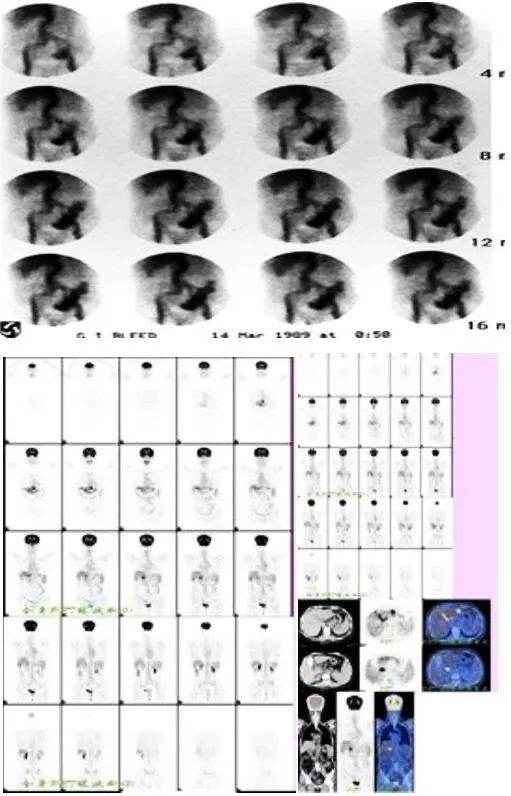

放射性核素消化道显像就能显示其定性和定位诊断作用。

核医学显像可作为各种原因所致下消化道出血的首选检查方法。具有简便、无创、灵敏、准确且便于动态观察,尤其是对下消化道出血患者。